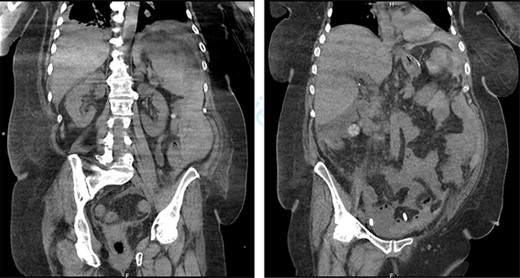

First, we embolized the splenic artery with coils (Fig. 3). The patient was getting well at intensive unit care, but few hours after embolization, she was shocked again.

We decided then to perform an emergency laparotomy that revealed a massive splenic hematoma and a totally burst spleen. We carried out the splenectomy and controlled the splenic vessels.